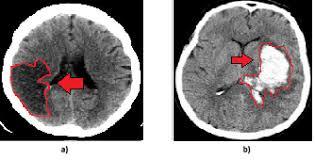

TOMOGRAFIA COMPUTADORIZADA

Princípior básico?

RAIO X

ou seja, o padrão de densidades segue o mesmo da radiográfia

Vantagens sobre a radiografia?

NÃO SOBREPÕE IMAGEM (CORTE AXIAL)

PODE CONSTRUIR IMAGENS

PODE FAZER JANELAS (OSSÉA E PARTES MOLES)

DENSIDADE MEDIDA EM UH

As nomenclaturas podem ser?

HIPERDENSAS (BRANCAS)

ISODENSAS

HIPODENSAS (PRETAS)